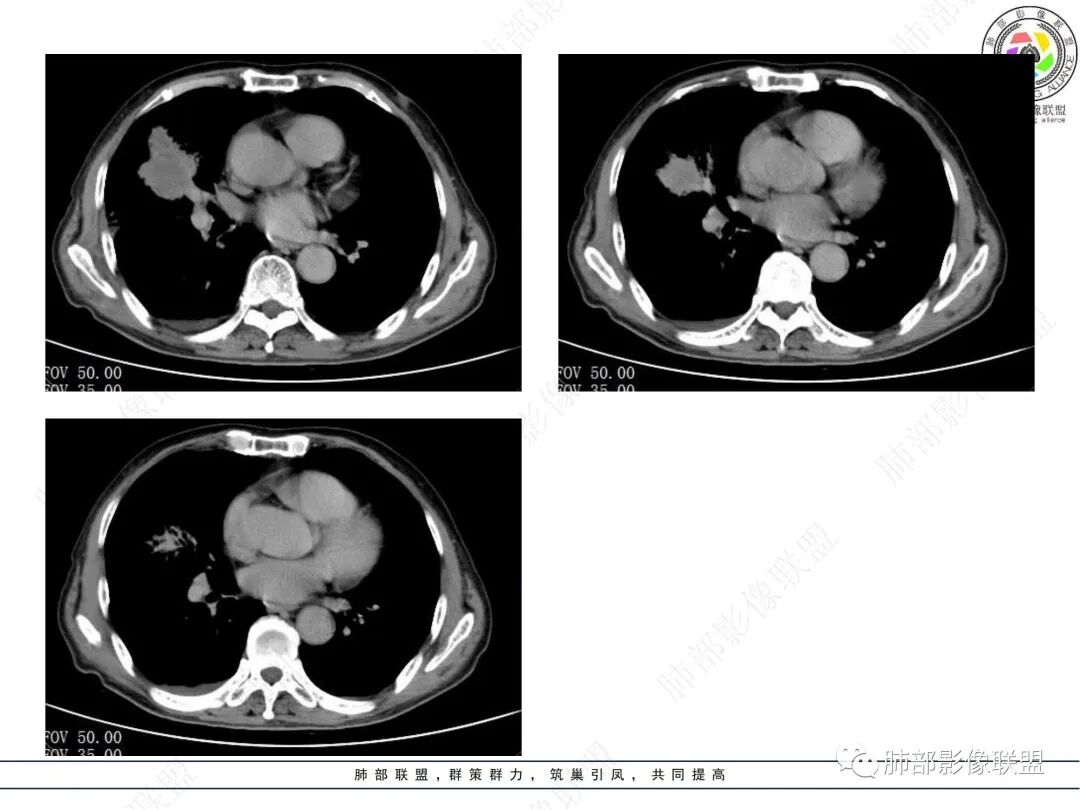

晨读病例,老年男性,乏力,纳差,近来发热,右肺上叶团片状阴影,内见空洞,空洞内壁不光滑,见短液平,增强病灶壁可见不均匀强化,似有边界不清晰的坏死,病灶周围可见片状模糊阴影,考虑恶性病变,鳞癌或腺癌伴感染。

老年男性,肺气肿背景,右肺较大分叶状肿块,密度不均,内坏死空洞形成,坏死区边界不规则,周围多发斑片蜂窝状、网格状高密度影,考虑鳞癌合并感染

老年男性,有咳嗽发热。右肺中上叶团状软组织肿块,周围磨玻璃渗出改变,病灶内密度不均,可见低密度坏死及空洞影,空洞内壁凹凸不平,近肺门侧可见明显大面积坏死。近端支气管堵塞不明显。考虑恶性肿瘤伴感染,腺癌?鉴别鳞癌,感染性病变。

70岁男性,发烧病史,右肺巨大肿块,边缘分叶,内部空洞,洞内见附壁结节,局部支气管阻塞,肿块周围见大片阻塞性炎症;实验室检查,炎性指标增高;考虑恶性肿瘤伴阻塞性肺炎,鳞癌可能。

老年男性,肺气肿背景,右肺上叶及中叶大范围实变影,边界不清,支气管通畅,其内见边缘膨隆软组织块影伴不规则坏死、空洞,增强扫描不均匀强化,洞壁显示不清,血管稍变细,实变影内另见多发囊样影,右肺下叶小片状影,病灶跨叶,炎性指标增高,感染应该有的,不除外合并恶性肿瘤(鳞癌?腺癌?)

男,70,反复乏力、纳差20天,发热1天。胸部CT:肺气肿背景,右肺上叶中叶大团片影,实变十磨玻璃渗出。增强实性斑片影内密度不均,可见多发低密度坏死及不规则空洞影,空洞内壁尚光滑,血管边缘模糊。支气管管壁增厚,管腔通畅。右下叶可见小片渗出影。考虑支气管肺炎进展?病原考虑能形成肉芽肿、坏死空洞的微生物,TB?奴卡?鉴别鳞癌。

老年男性,乏力纳差,进食量明显下降,发热,后期少许黄脓痰,无咯血。无胸痛。未提口腔卫生情况,发热时间段不明确,肺气肿背景,气管内痰拴还是其他?觉得是外朝内进展病灶,右肺多叶段病灶,支气管通畅,支气管壁弥漫增厚,实变病灶内有坏死,坏死边界比较清晰,血管破坏不明显,周围散在磨玻璃,边界模糊,无树芽,实变内可疑小钙化,右侧胸水,肺门纵隔淋巴结无明显肿大。病史不太支持化脓菌感染,真菌里隐球强化不太支持,结核需要排除,厌氧菌感染带排,冠状位矢状位病灶觉得类圆形,临床肿瘤也是不能轻易排除的

两个病灶独立,又有关联性,内侧病灶近端的支气管包绕在外侧病灶之中,但是走形自然

内部大片坏死区,其中还有不规则空洞

坏死腔内壁清,有强化环

肺动脉在实变区走形自然,坏死腔周围受压推移,走形自然,坏死区内破坏